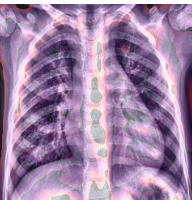

The last example, in Figure 5d) is blurred. The image of the lungs is improperly taken, and the process should be repeated. The current image is useless for the accurate diagnosis process. Such images should be removed during data resource verification before model training.